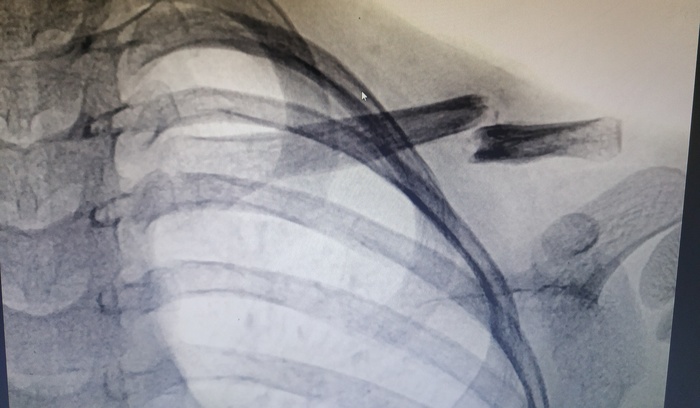

Поэтому я решил представить вам пример успешной репарации ключицы у ребенка 6 лет:

Ребра упал с высоты собственного роста. Обратился в трпункт где был выставлен диагноз : Закрытый перелом ключицы с допустимым смещением,- иммобилизация и отпущен домой с рекомендациями(контрольная рентгенография ,покой и ТД)

Через неделю (кажется ,что просто п ****ц взрослые травматологи падают в обморок НО реально ребенка ничего не беспокоит ; смена повязки на покупную и в поликлинику по м/ж)

Через 6 месяцев

Всё срослось .Из остаточного лишь утолщение кости ,которое исчезнет со временем)

N.B. Вылечить перелом ключицы у детей дошкольного возраста достаточно просто ведь этим заниматься сам организм ) За время работы несращения или замедленной консолидации у дошколят не видел .

Если посмотреть на 2 снимок то увидите облачко вокруг концов отломков!это зарождается первичная мозоль ,которая выходит из гематомы(кровяного сгустка) как Венера из океана)